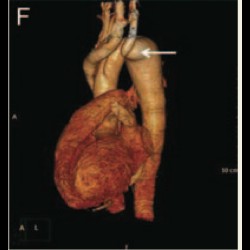

Supra-valvular aortic stenosis in a patient with homozygous familial hypercholesterolaemia

Supra-valvular aortic stenosis in a patient with homozygous familial hypercholesterolaemia

Supra-valvular aortic stenosis in a patient with homozygous familial hypercholesterolaemia

Supra-valvular aortic stenosis in a patient with homozygous familial hypercholesterolaemia